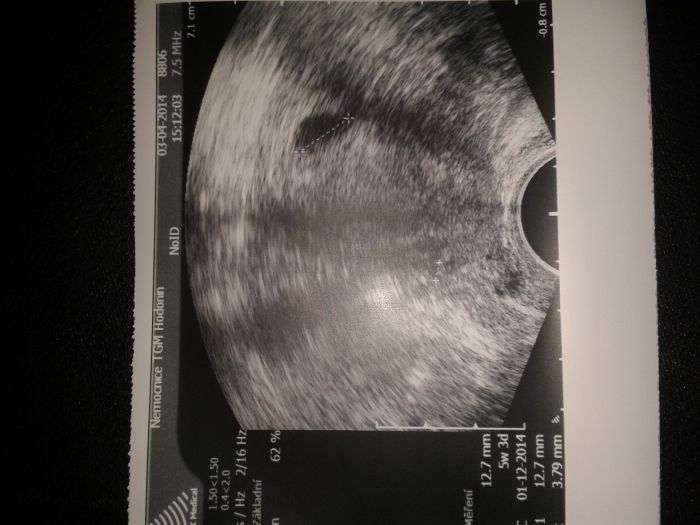

Zdravim vsechny tehulky.dnes byla na ultrazvuku a jsem 5tyden, podle MS jsem zacatek 8.srdicko jeste neni.pan doktor ma stary ultrazvuk a tak na fotce jde mimi spatne videt, ale urcite tam je.v utery jdu znovu na ultrazvuk tak snad bude videt vic.

Ivet, je tam žloutkový váček, prcek bude vidět později